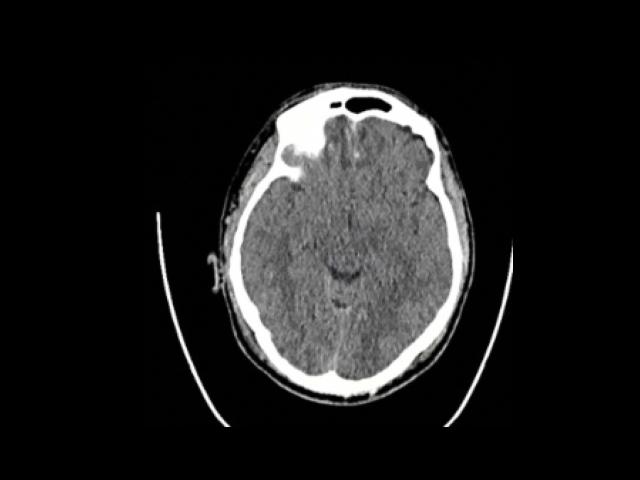

Sample Gallery